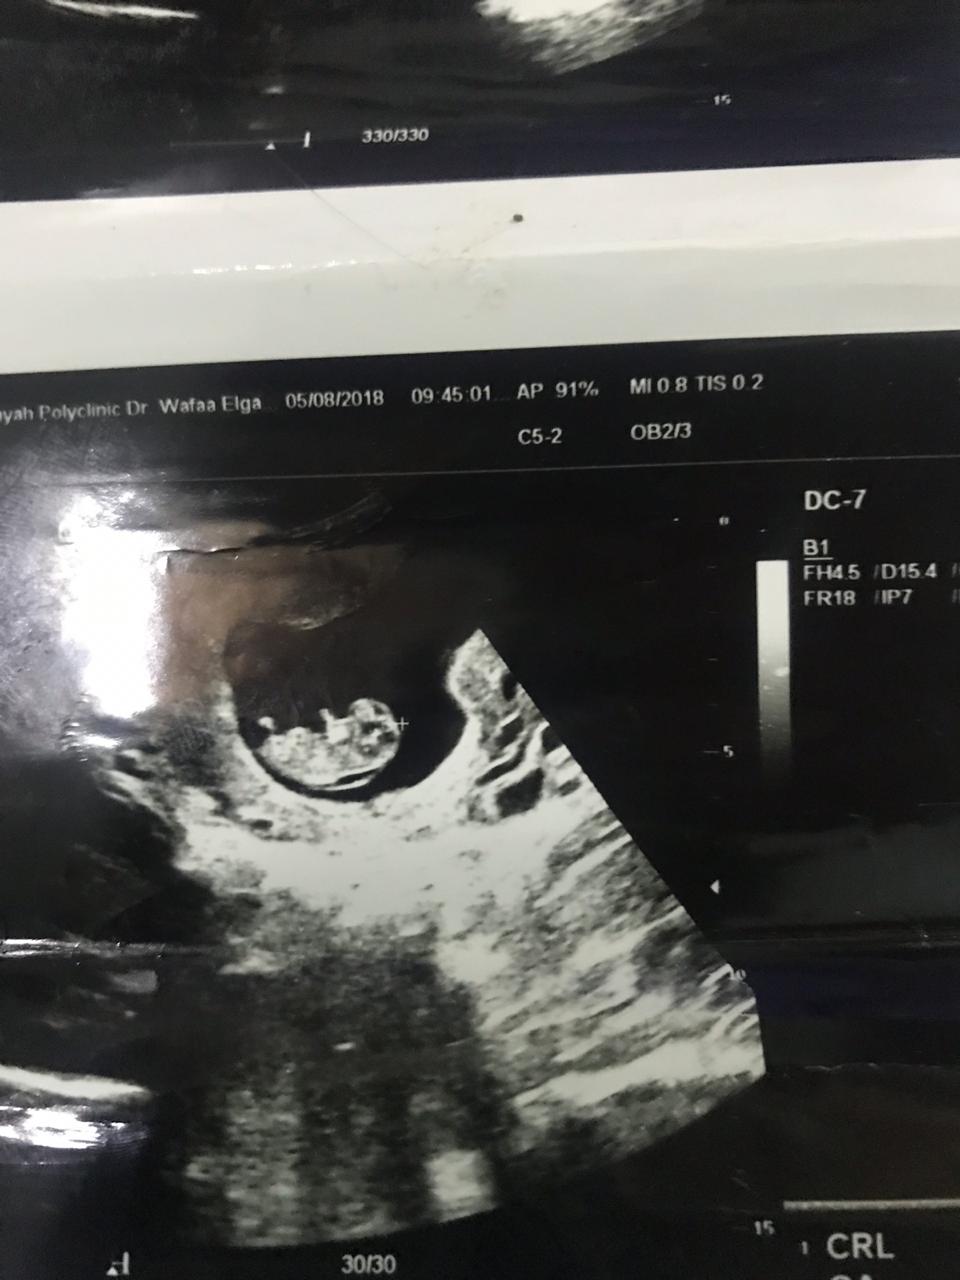

⭐- يعتمد الفحص على قياس سماكة الشفافية القفوية بإستخدام الأشعة الصوتية (السونار)

وهو عبارة عن تجمع سوائل في منطقة رقبة الجنين ويكون في فترة الحمل من 10 إلى 14 أسبوع تقريبًا

أو إذا كان طول الجنين من 36 إلى 84 ملم.